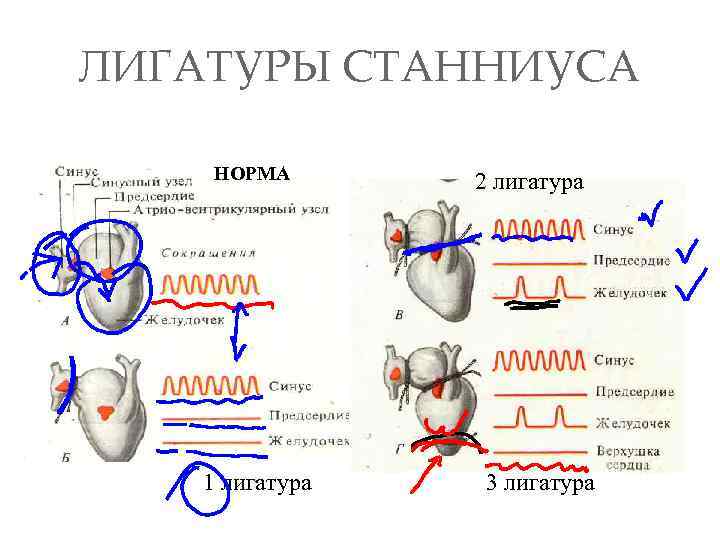

ЛИГАТУРЫ СТАННИУСА НОРМА 1 лигатура 2 лигатура 3 лигатура

ЛИГАТУРЫ СТАННИУСА НОРМА 1 лигатура 2 лигатура 3 лигатура

Кардиограмма предсердий (верхняя кривая) и желудочков лягушки после наложения второй лигатуры Станниуса

Кардиограмма предсердий (верхняя кривая) и желудочков лягушки после наложения второй лигатуры Станниуса